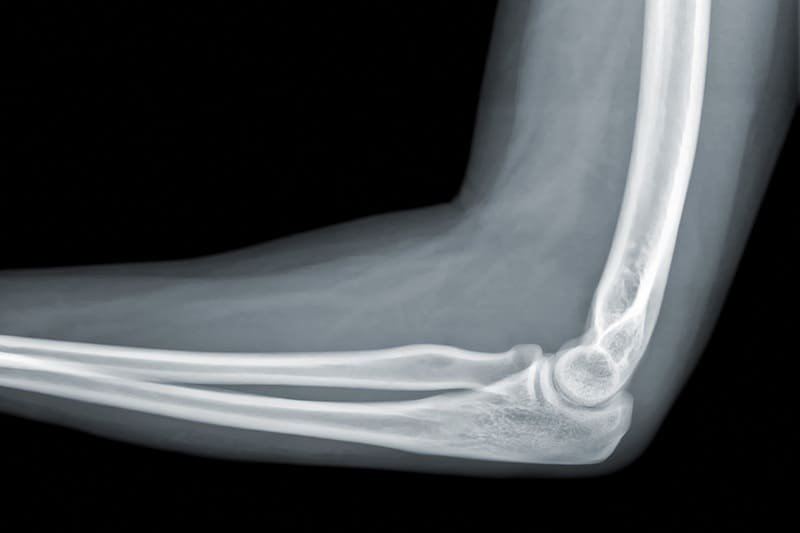

La Radiografía de codo en Guadalajara, Jalisco es un estudio esencial para evaluar lesiones óseas, fracturas, luxaciones o alteraciones articulares en esta zona. Es comúnmente solicitada después de caídas, golpes directos o accidentes deportivos, ya que permite observar con claridad el húmero, radio y cúbito. La Radiografía de codo en Guadalajara, Jalisco a domicilio se realiza con equipo portátil moderno, brindando comodidad, rapidez y resultados confiables sin necesidad de acudir a un hospital.

La Radiografía de codo en Guadalajara, Jalisco se recomienda cuando existe dolor persistente, inflamación, dificultad para extender o flexionar el brazo, o sospecha de fractura tras un traumatismo. También es útil para seguimiento ortopédico, control de lesiones por esfuerzo repetitivo o valoración de artritis. Realizar la Radiografía de codo en Guadalajara, Jalisco en casa facilita la atención de adultos mayores, pacientes con movilidad limitada o personas que requieren diagnóstico rápido sin traslados.

Sí, la Radiografía de codo en Guadalajara, Jalisco permite identificar fracturas, fisuras y alteraciones óseas con alta precisión. Es especialmente útil en lesiones deportivas o traumatismos, ya que ayuda a definir el tratamiento adecuado y prevenir complicaciones durante la recuperación.